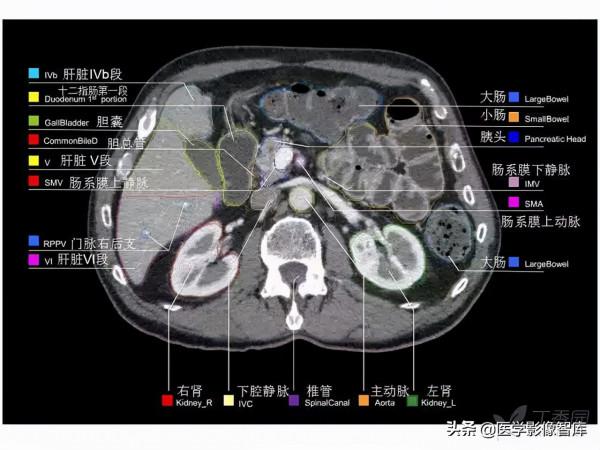

腹部CT